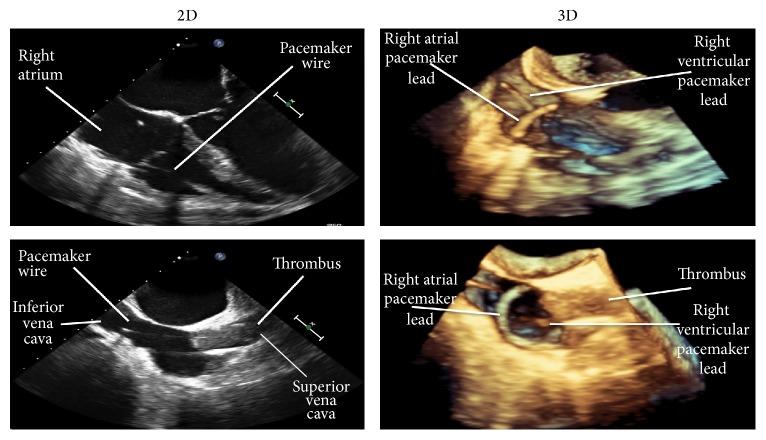

Three-dimensional (3D) echocardiography is becoming widely available and with novel applications. We report an interesting case of a 68-year-old lady with a central venous thrombosis coincident with both a dialysis catheter infection and a recent pacemaker insertion. Two-dimensional transesophageal echocardiography was unable to delineate whether the thrombosis was involved with the pacemaker wire or due to the tunneled catheter infection. The use of 3D echocardiography was able to produce distinct images aiding diagnosis. This circumvented the need for invasive investigations and inappropriate, high-risk removal of the pacing wire. This case highlights the emerging application of 3D echocardiography in routine nephrology practice.